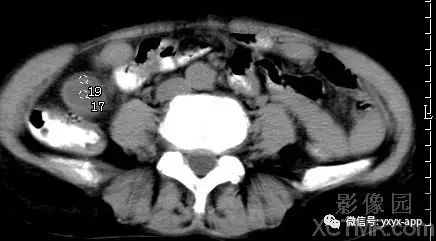

【病史临床】女性,66岁,右下腹胀痛不适一月。

CT影像表现:右下腹囊性肿块,囊液密度均匀,囊壁规整,增强囊壁有强化,周围肠腔无梗阻征象,考虑阑尾粘液囊肿或肠系膜囊肿。

最后结果:手术病理:阑尾粘液囊肿。